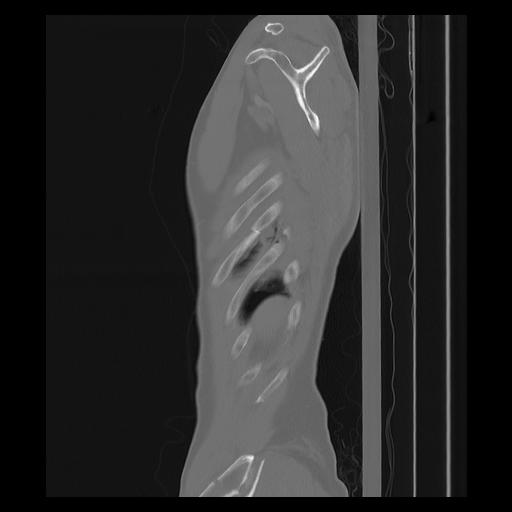

33 PULMON,CE,Sagittal,3.000,PULMON,Sagittal,